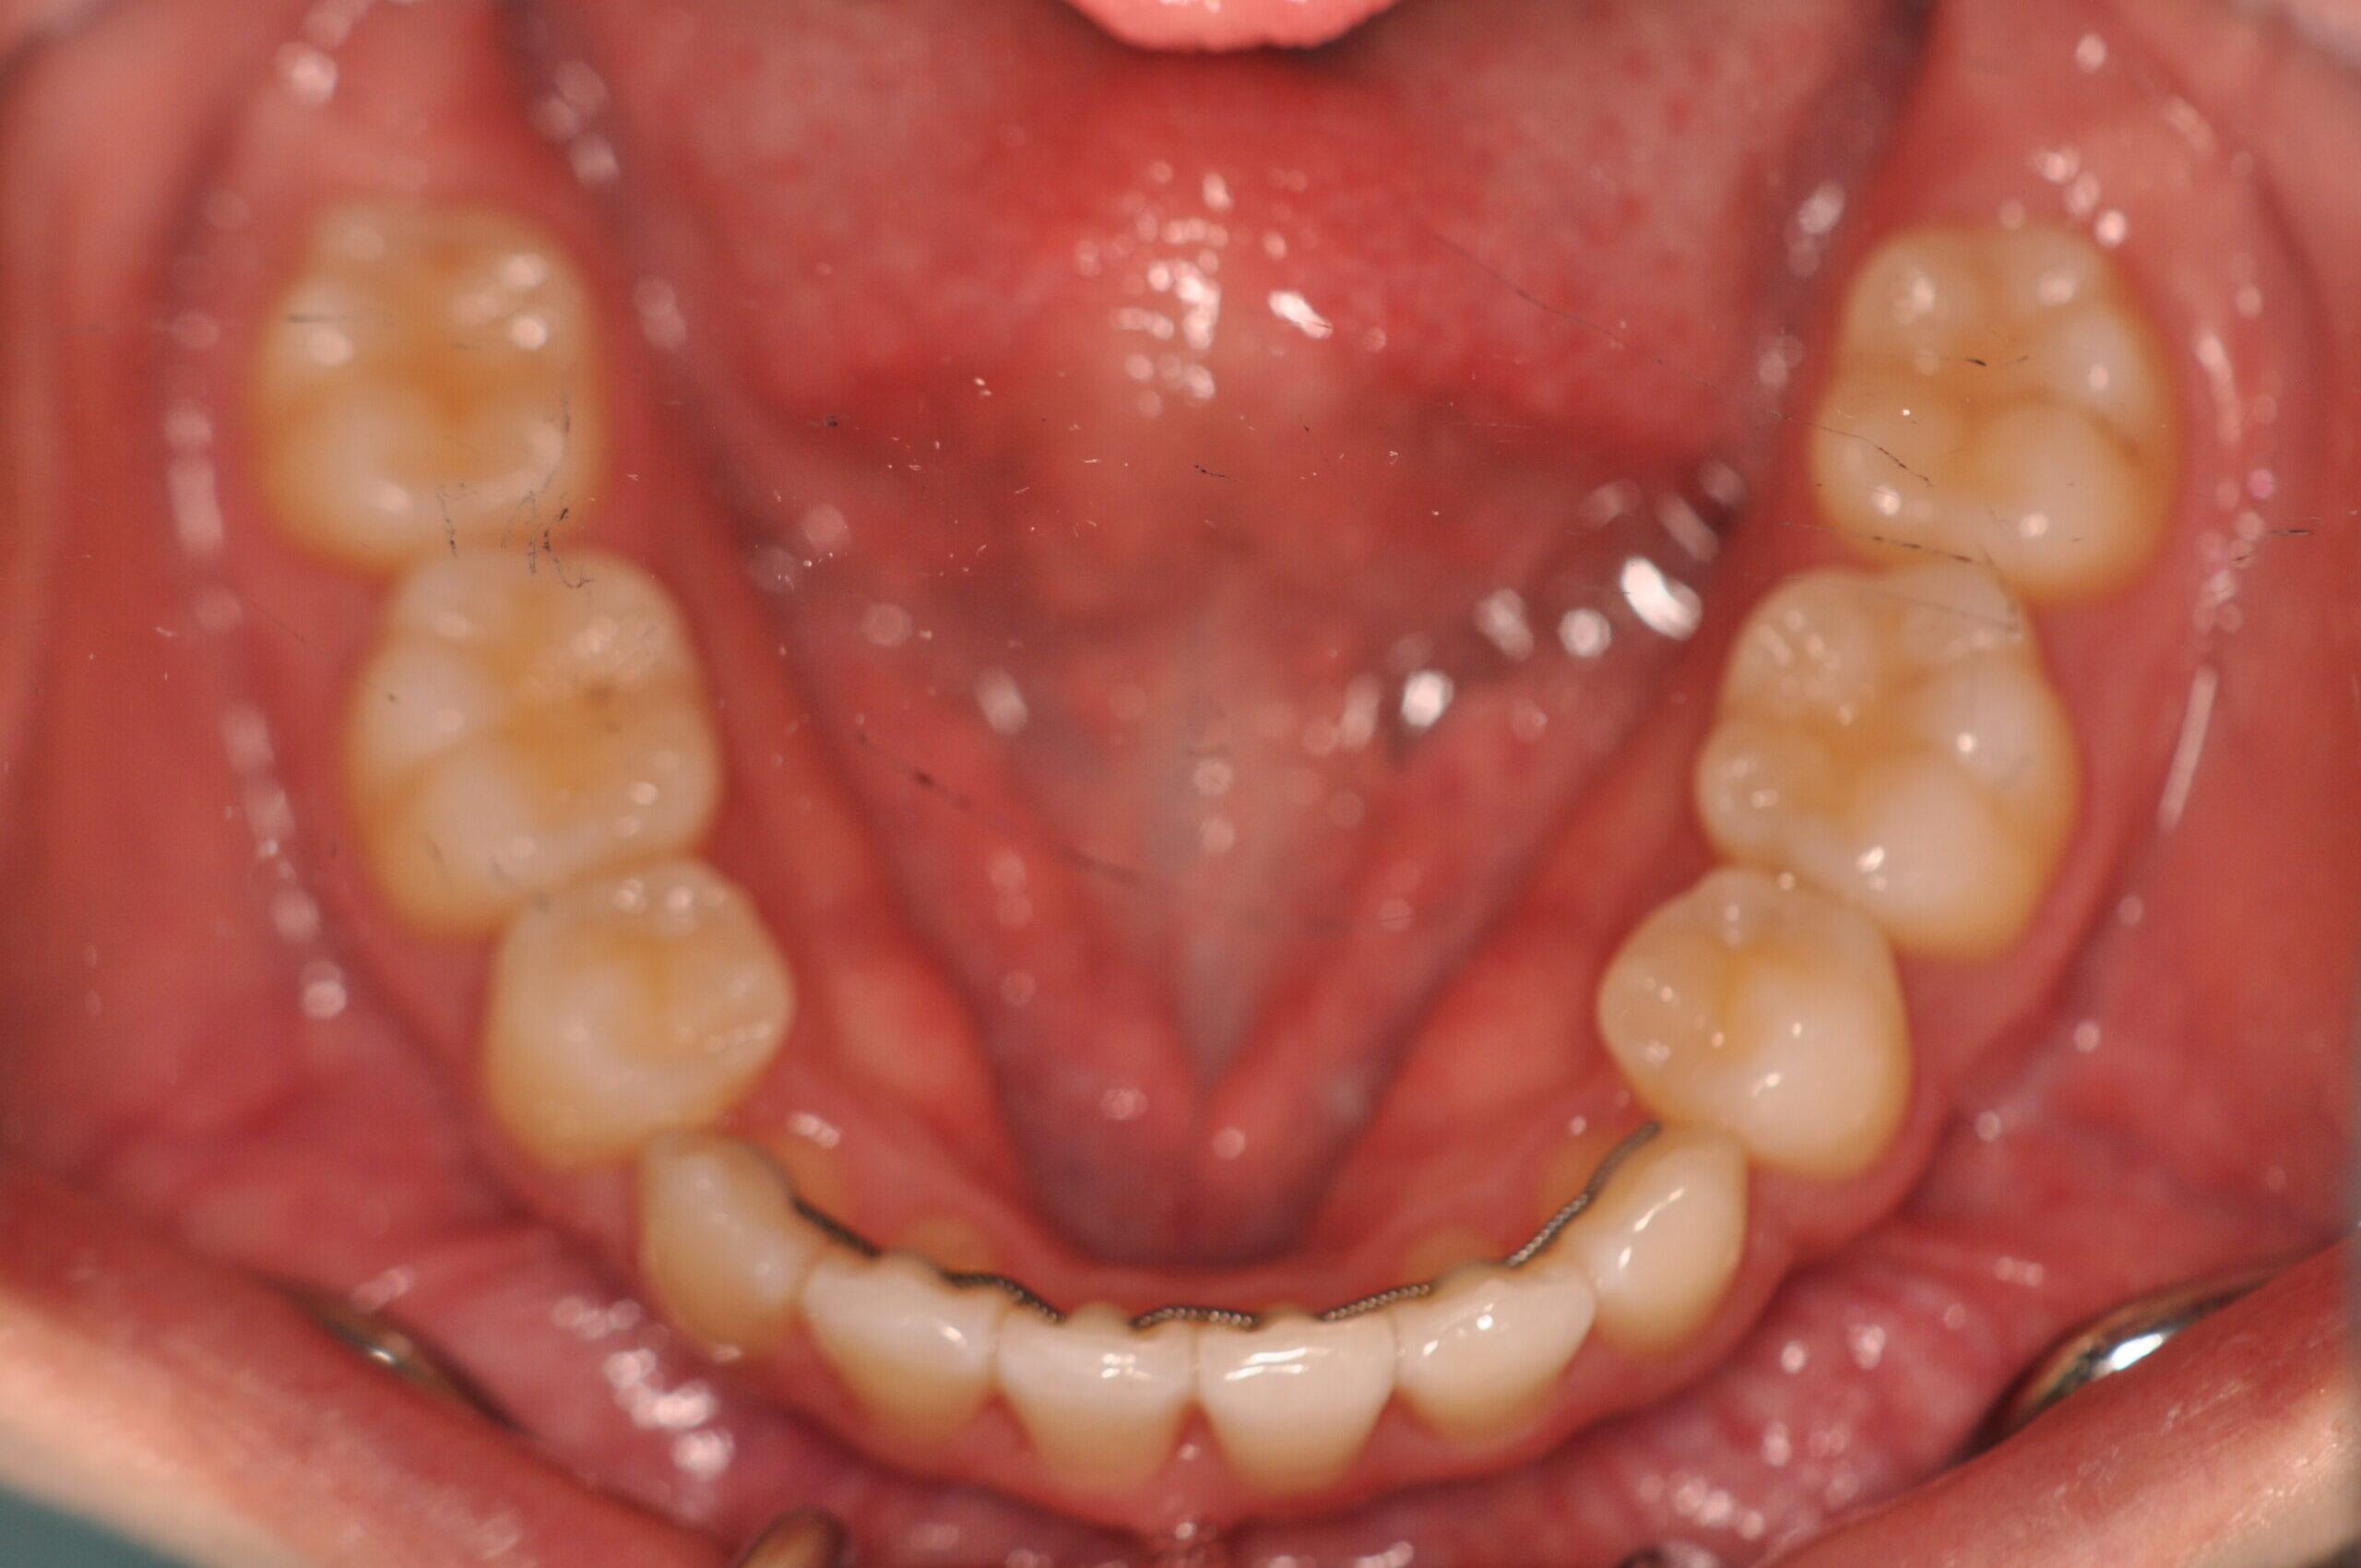

でっ歯(抜歯)【2247】

動的治療終了時

治療内容の詳細 初診時20歳の女性で、出っ歯、歯のがたつきを気にされ来院しました。

検査の結果、上下顎前歯部叢生を伴うアングルⅠ級不正咬合と診断しました。

治療としては、上下左右第一小臼歯を抜歯の上、セルフライゲーションブラケット装置(デーモンシステム)と

マウスピース矯正装置(インビザライン)で配列を行いました。

この際、上顎に歯科矯正用アンカースクリューを設置し上顎前歯部後退時の土台としました。

治療期間は2年1ヶ月でした。